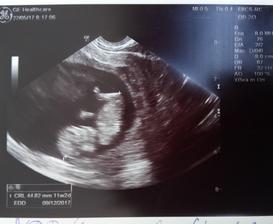

22.5.2017 - třetí kontrola a fotečka 🙂 vše v pořádku, dostala jsem utrogestan